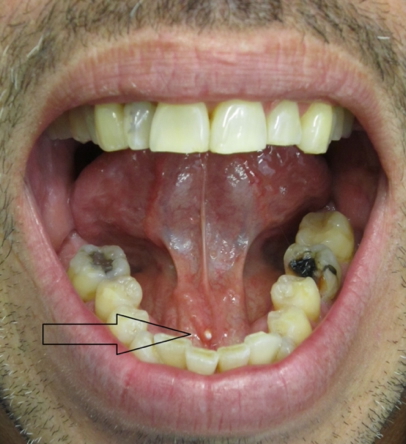

- Palpable calculus on intraoral examination (often floor of mouth for submandibular stones)